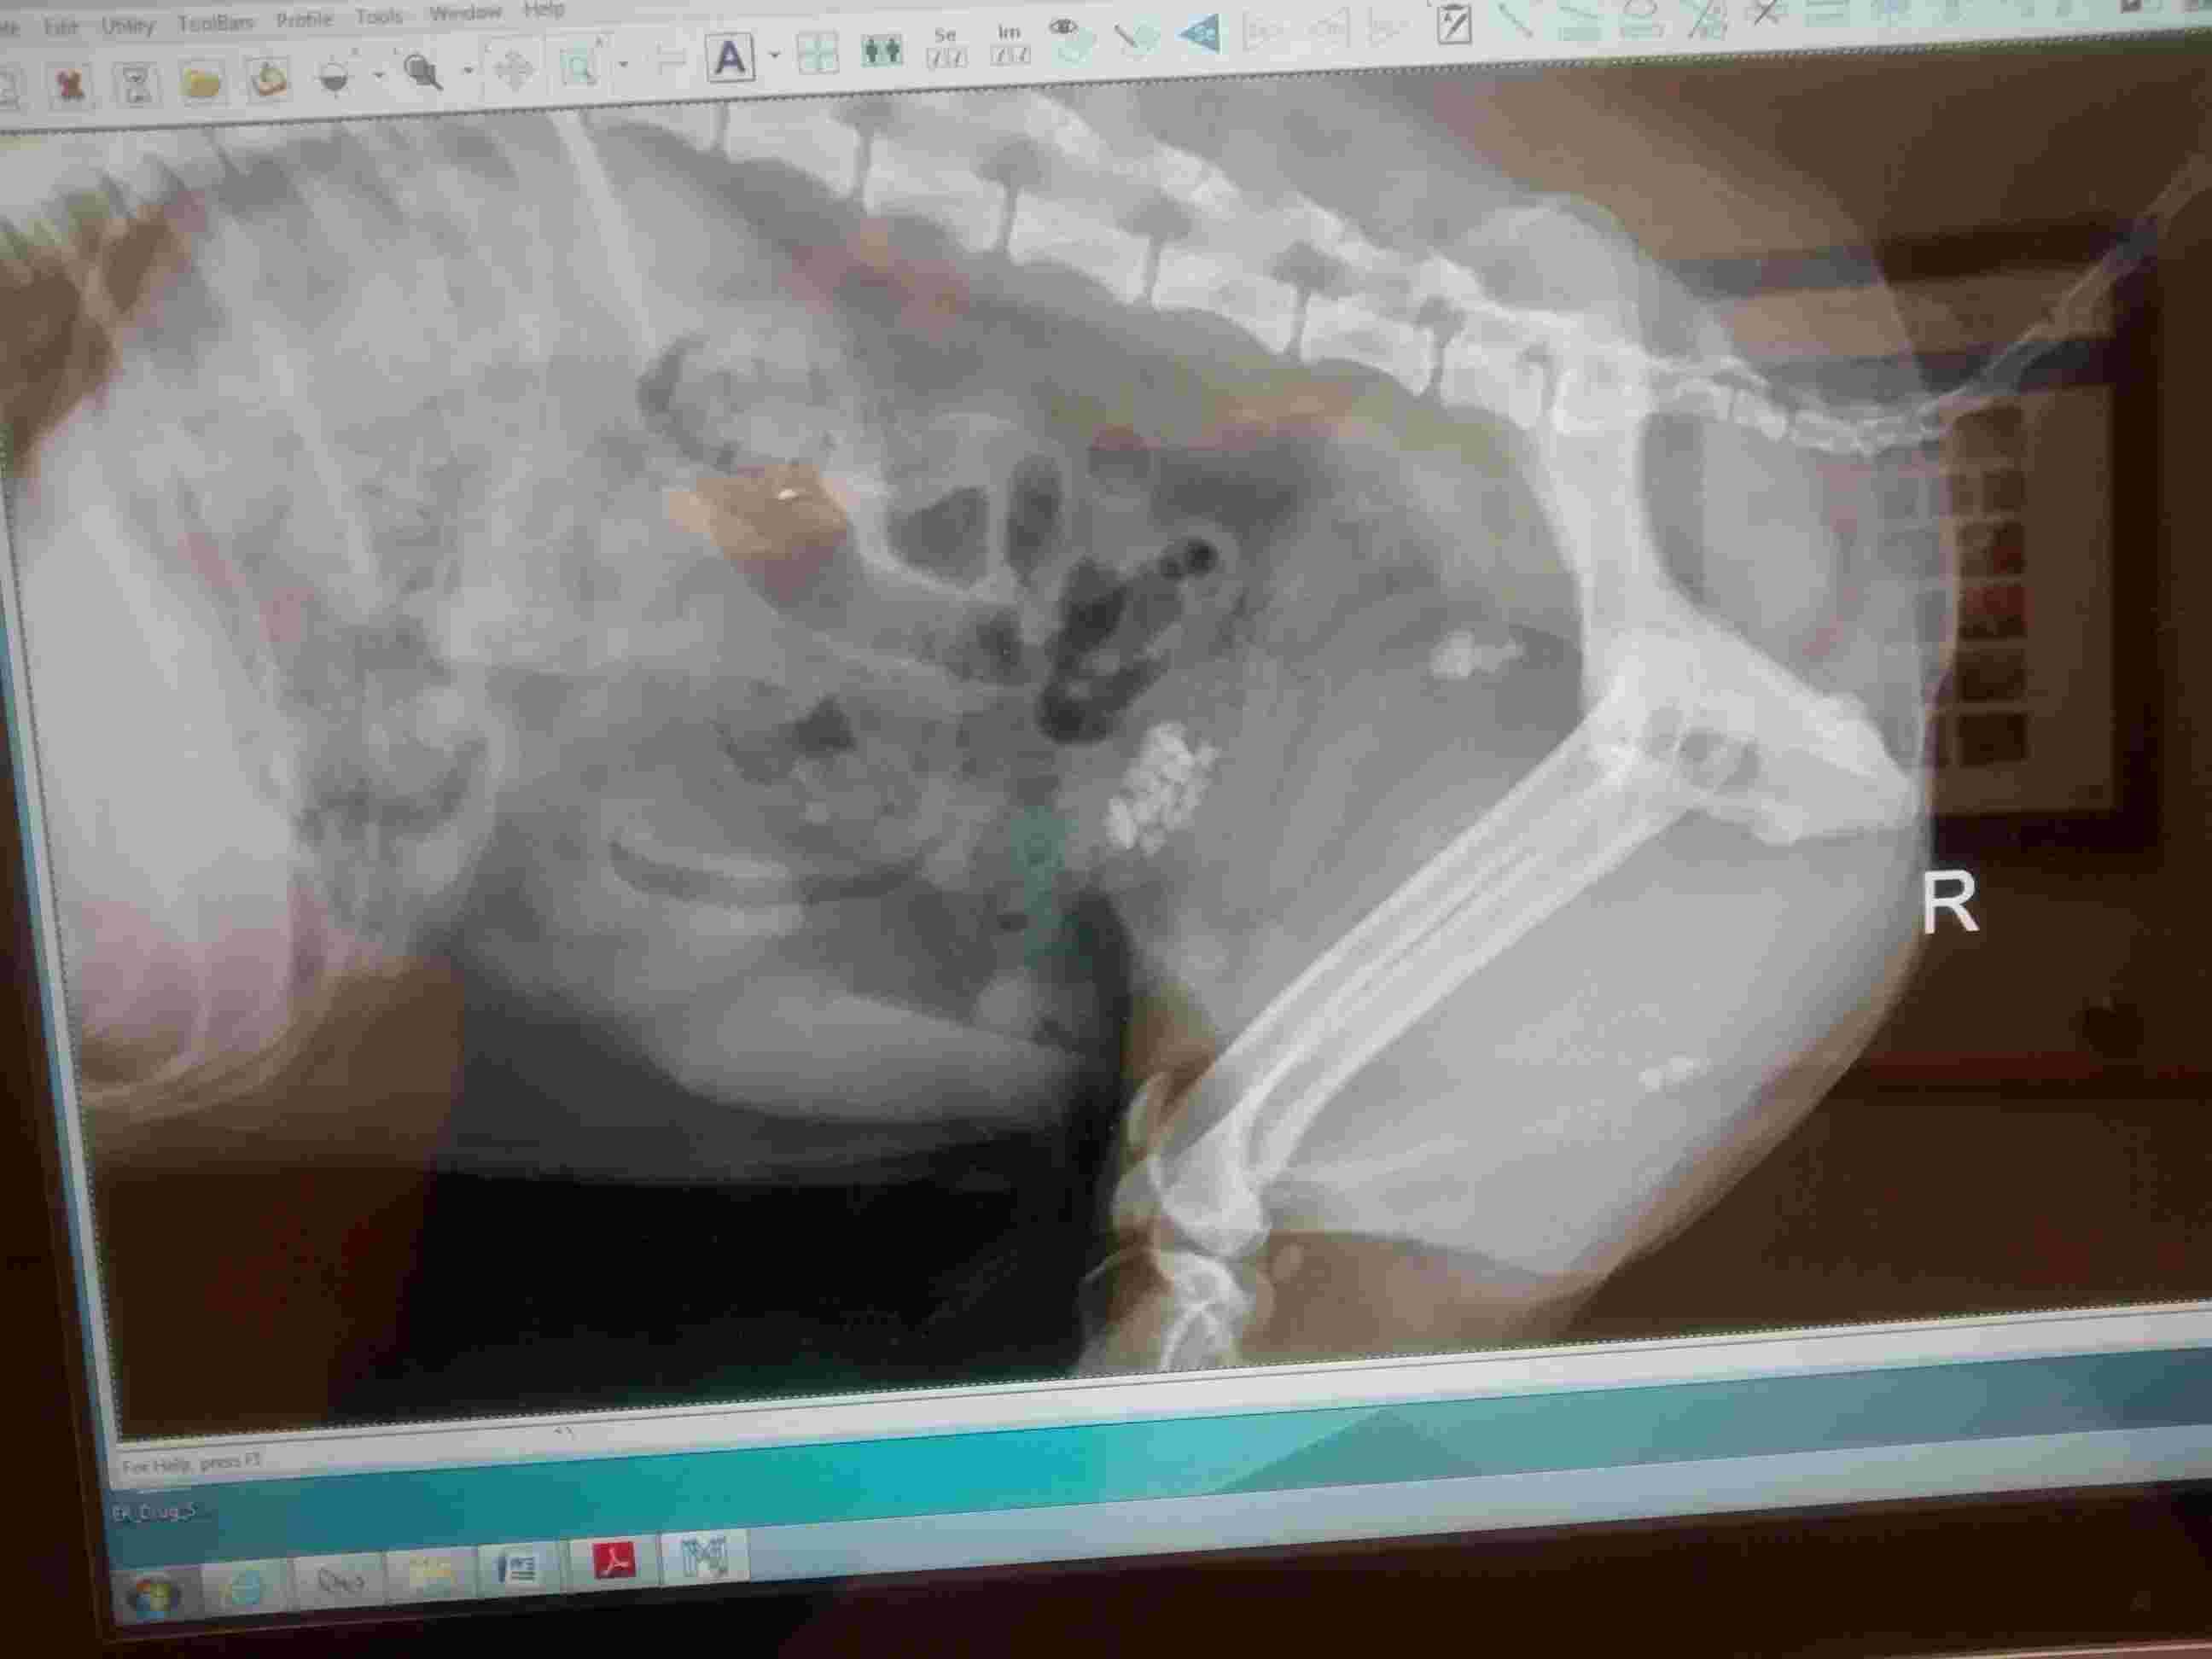

Hello. My 9 y.o terrier was not able to urinate. This is his x ray at the time of the incidence. Emergency surgery was not available so he was put down. I am heartbroken and his prognosis was never explained to me. Can you please review the x ray and help me understand what was happening?

I am very sorry to hear about your dog. The X-ray is slightly pixelated on our side so difficult to fully interpret but it looks like there are stones in the bladder and probably also the urethra (tiny tube that connects bladder to the outside). The stones in the urethra were likely causing blockage leading to inability to urinate. Sometimes we can pass a urinary catheter to relieve the blockage temporarily by pushing the stones back into the bladder, where they can be removed surgically, and the catheter can allow urination until that time. In some cases however the stones will not allow passage of the catheter in which case surgery may be much more complicated. I cannot speak to the circumstances in your dog or the hospital capabilities. I would recommend making an appointment to talk to the vet about what happened to have closure. I am sorry for your loss.